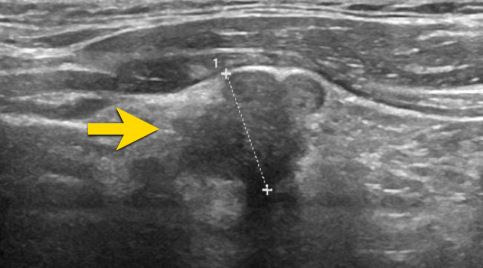

Siêu âm là phương pháp hình ảnh không xâm lấn, an toàn và chính xác. Siêu âm giúp:

-

Phát hiện bướu nhân tuyến giáp dù kích thước nhỏ <5mm.

Phân biệt nhân lành tính hay nghi ngờ ác tính dựa vào cấu trúc, bờ viền, vi vôi hóa.

Hướng dẫn chọc hút tế bào bằng kim nhỏ (FNA) khi cần.

Hình ảnh siêu âm nhân tuyến giáp